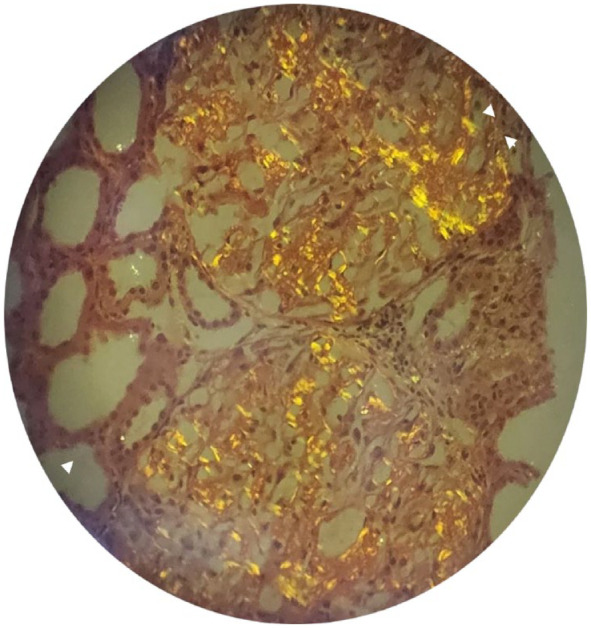

Familial Mediterranean fever (FMF) is an autosomal recessive disorder, particularly common in the Mediterranean area. Mutations in the MEVF gene cause it. AA Amyloidosis is the most severe complication of FMF leading to chronic renal failure. We describe a rare pediatric case of a phenotype I familial Mediterranean fever with V726A heterozygous mutation. The diagnosis was made at chronic kidney disease. We discuss through this case the importance of the early diagnosis of FMF heterozygous children which is not usually evident in some phenotypes. It will surely avoid fatal complications, inappropriate therapeutic approaches and higher healthcare costs.

Abstract Image